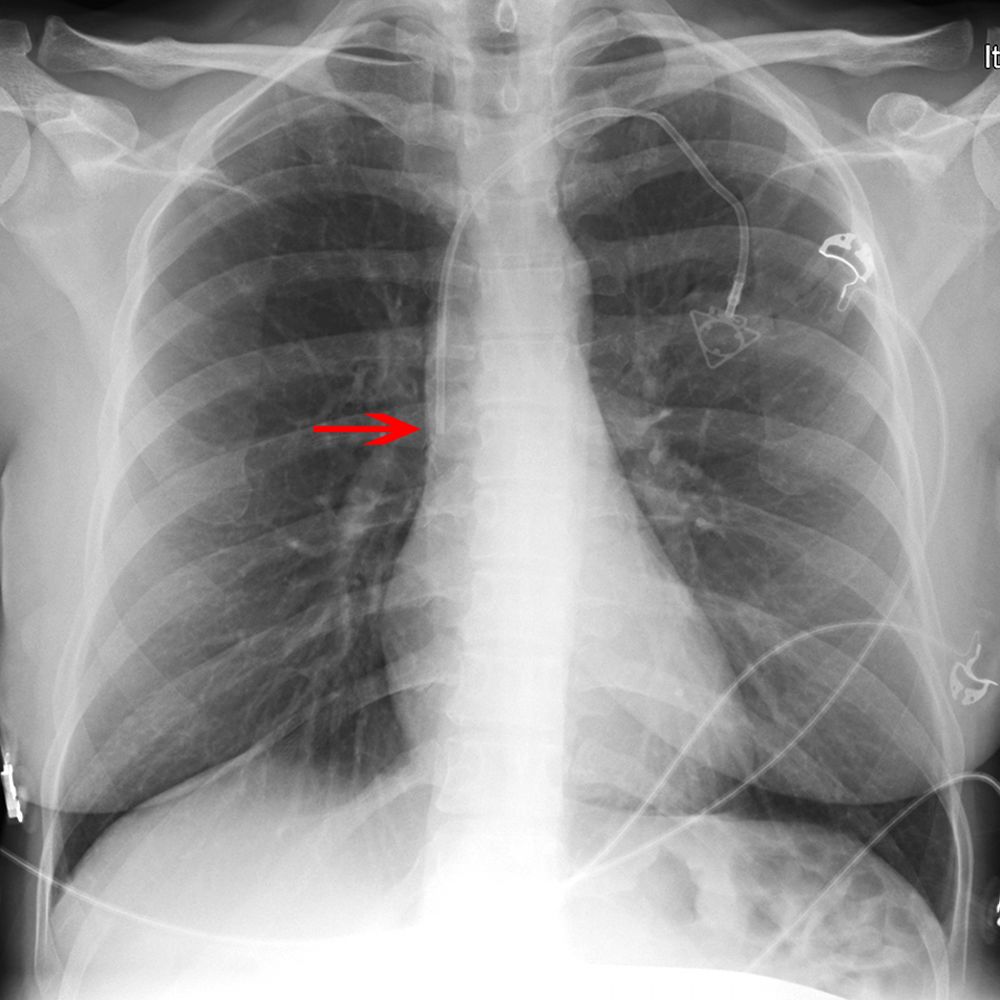

Anatomia della Radiografia del Torace Etichettata [Clinica] : r/medicalschool

Dottor - La sindrome della vena cava superiore è la più caratteristica e frequente delle sindromi mediastiniche e si ha quando viene ostacolato il deflusso di sangue dalla vena cava superiore al